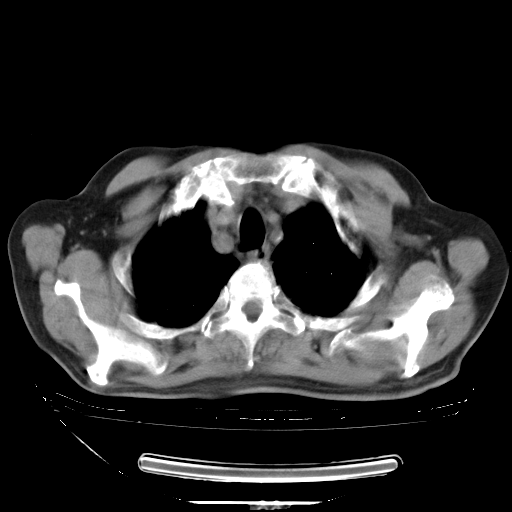

今天复查肺部CT,发现双肺广泛磨玻璃样改变。所以我把3月19日和5月9日相隔50天的肺部CT上传。请大家会诊。

5月9日肺部CT(在4月27日齐鲁医院肺部CT描述部分肺组织磨玻璃样改变,12天后肺组织广泛磨玻璃样改变)

2009年5月9日肺部CT

大致读了系列胸部CT:纵隔窗无明显异常,肺窗:从4、27至今:主要是双肺中下野外带可见毛玻璃样改变,目前处于急性肺泡炎阶段,至于原因考虑1、结替组织或胶原血管性疾病所致?2、恶性疾病如恶组在肺部所致的表现或细支气管肺泡癌?3、药物或其它原因如肺蛋白沉着症所致肺泡炎目前不太可能?总之,明天就去请我院的呼吸科、感染科、血液科和临免专家会诊哈。